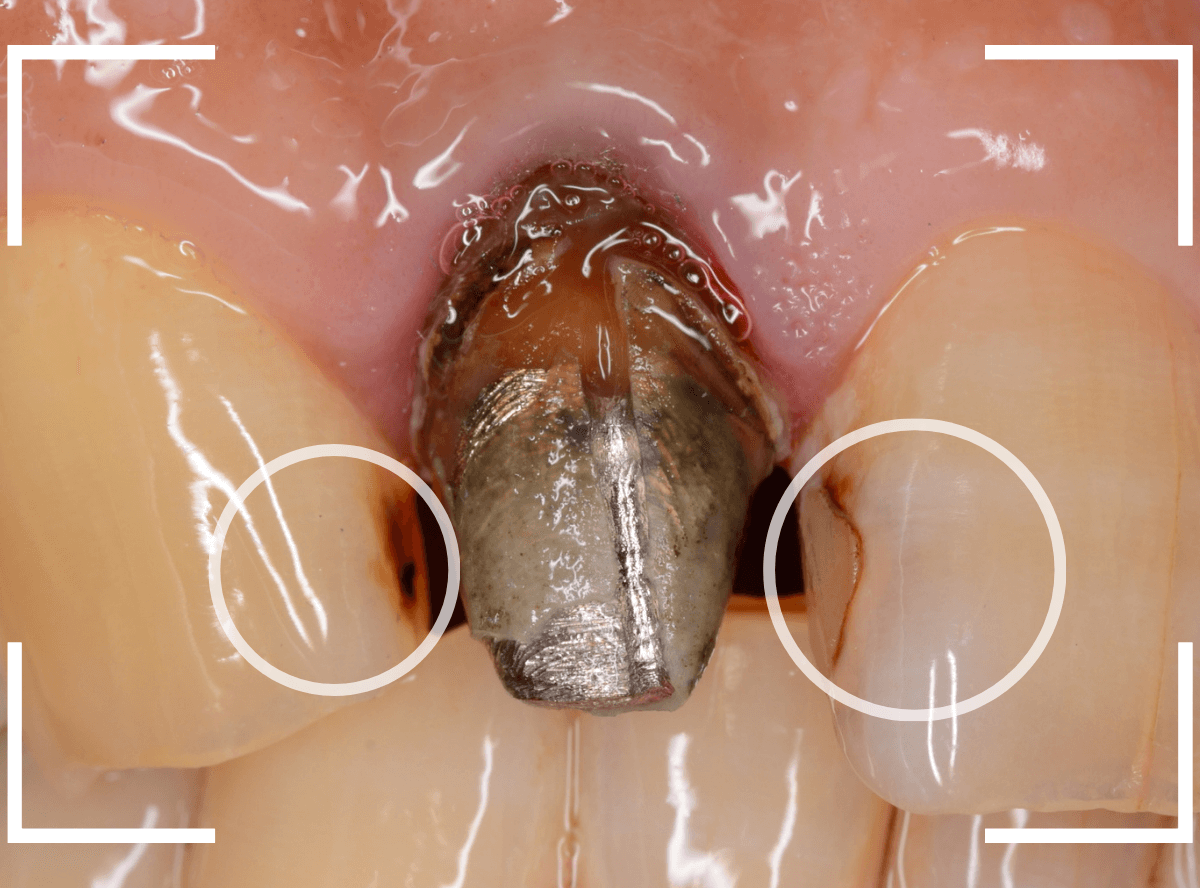

歯を裏側から見たところです。

幸い、見える部分に虫歯が

さし歯と歯肉の間に虫歯ができているのがわかります。

歯の奥まで虫歯が進んでいるのか、浅い虫歯ですんでいるのかは治療をしながら調べていく必要があります。

さし歯を外すと、金属の土台(メタル・コア)が出てきました。

慎重に土台を外して、中を調べます。